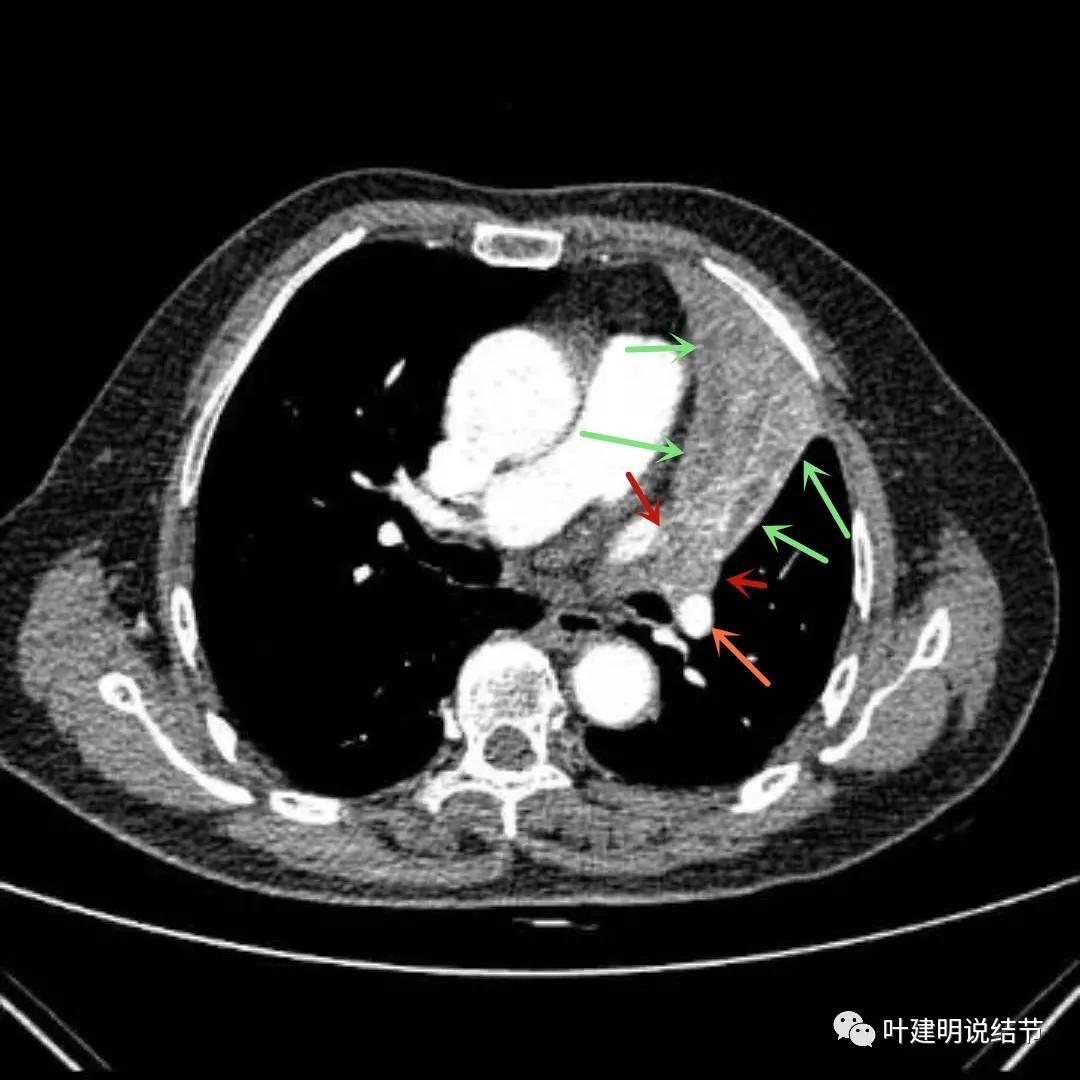

上图绿色箭头所指区域考虑为肺不张,红色示肿瘤处且有不均质与膨胀性,桔色箭头所指处显示肿瘤与肺动脉关系密切,考虑有侵犯肺动脉

上图绿色箭头所指区域考虑为肺不张,红色示肿瘤处且有不均质与膨胀性,桔色箭头所指处显示肿瘤与肺动脉关系密切,考虑有侵犯肺动脉。之所以肺动脉中间有软组织影,是因为肿瘤长到肺动脉与支气管之间的缝隙里,相当于血管是跨在肿瘤上,与肿瘤接触的这面是侵犯愈着的。

上图绿色箭头所指区域考虑为肺不张,红色示肿瘤处且有不均质与膨胀性,粉色箭头示左上叶开口处已经有肿瘤在,表面不平整。之所以肺动脉中间有软组织影,是因为肿瘤长到肺动脉与支气管之间的缝隙里,相当于血管是跨在肿瘤上,与肿瘤接触的这面是侵犯愈着的。